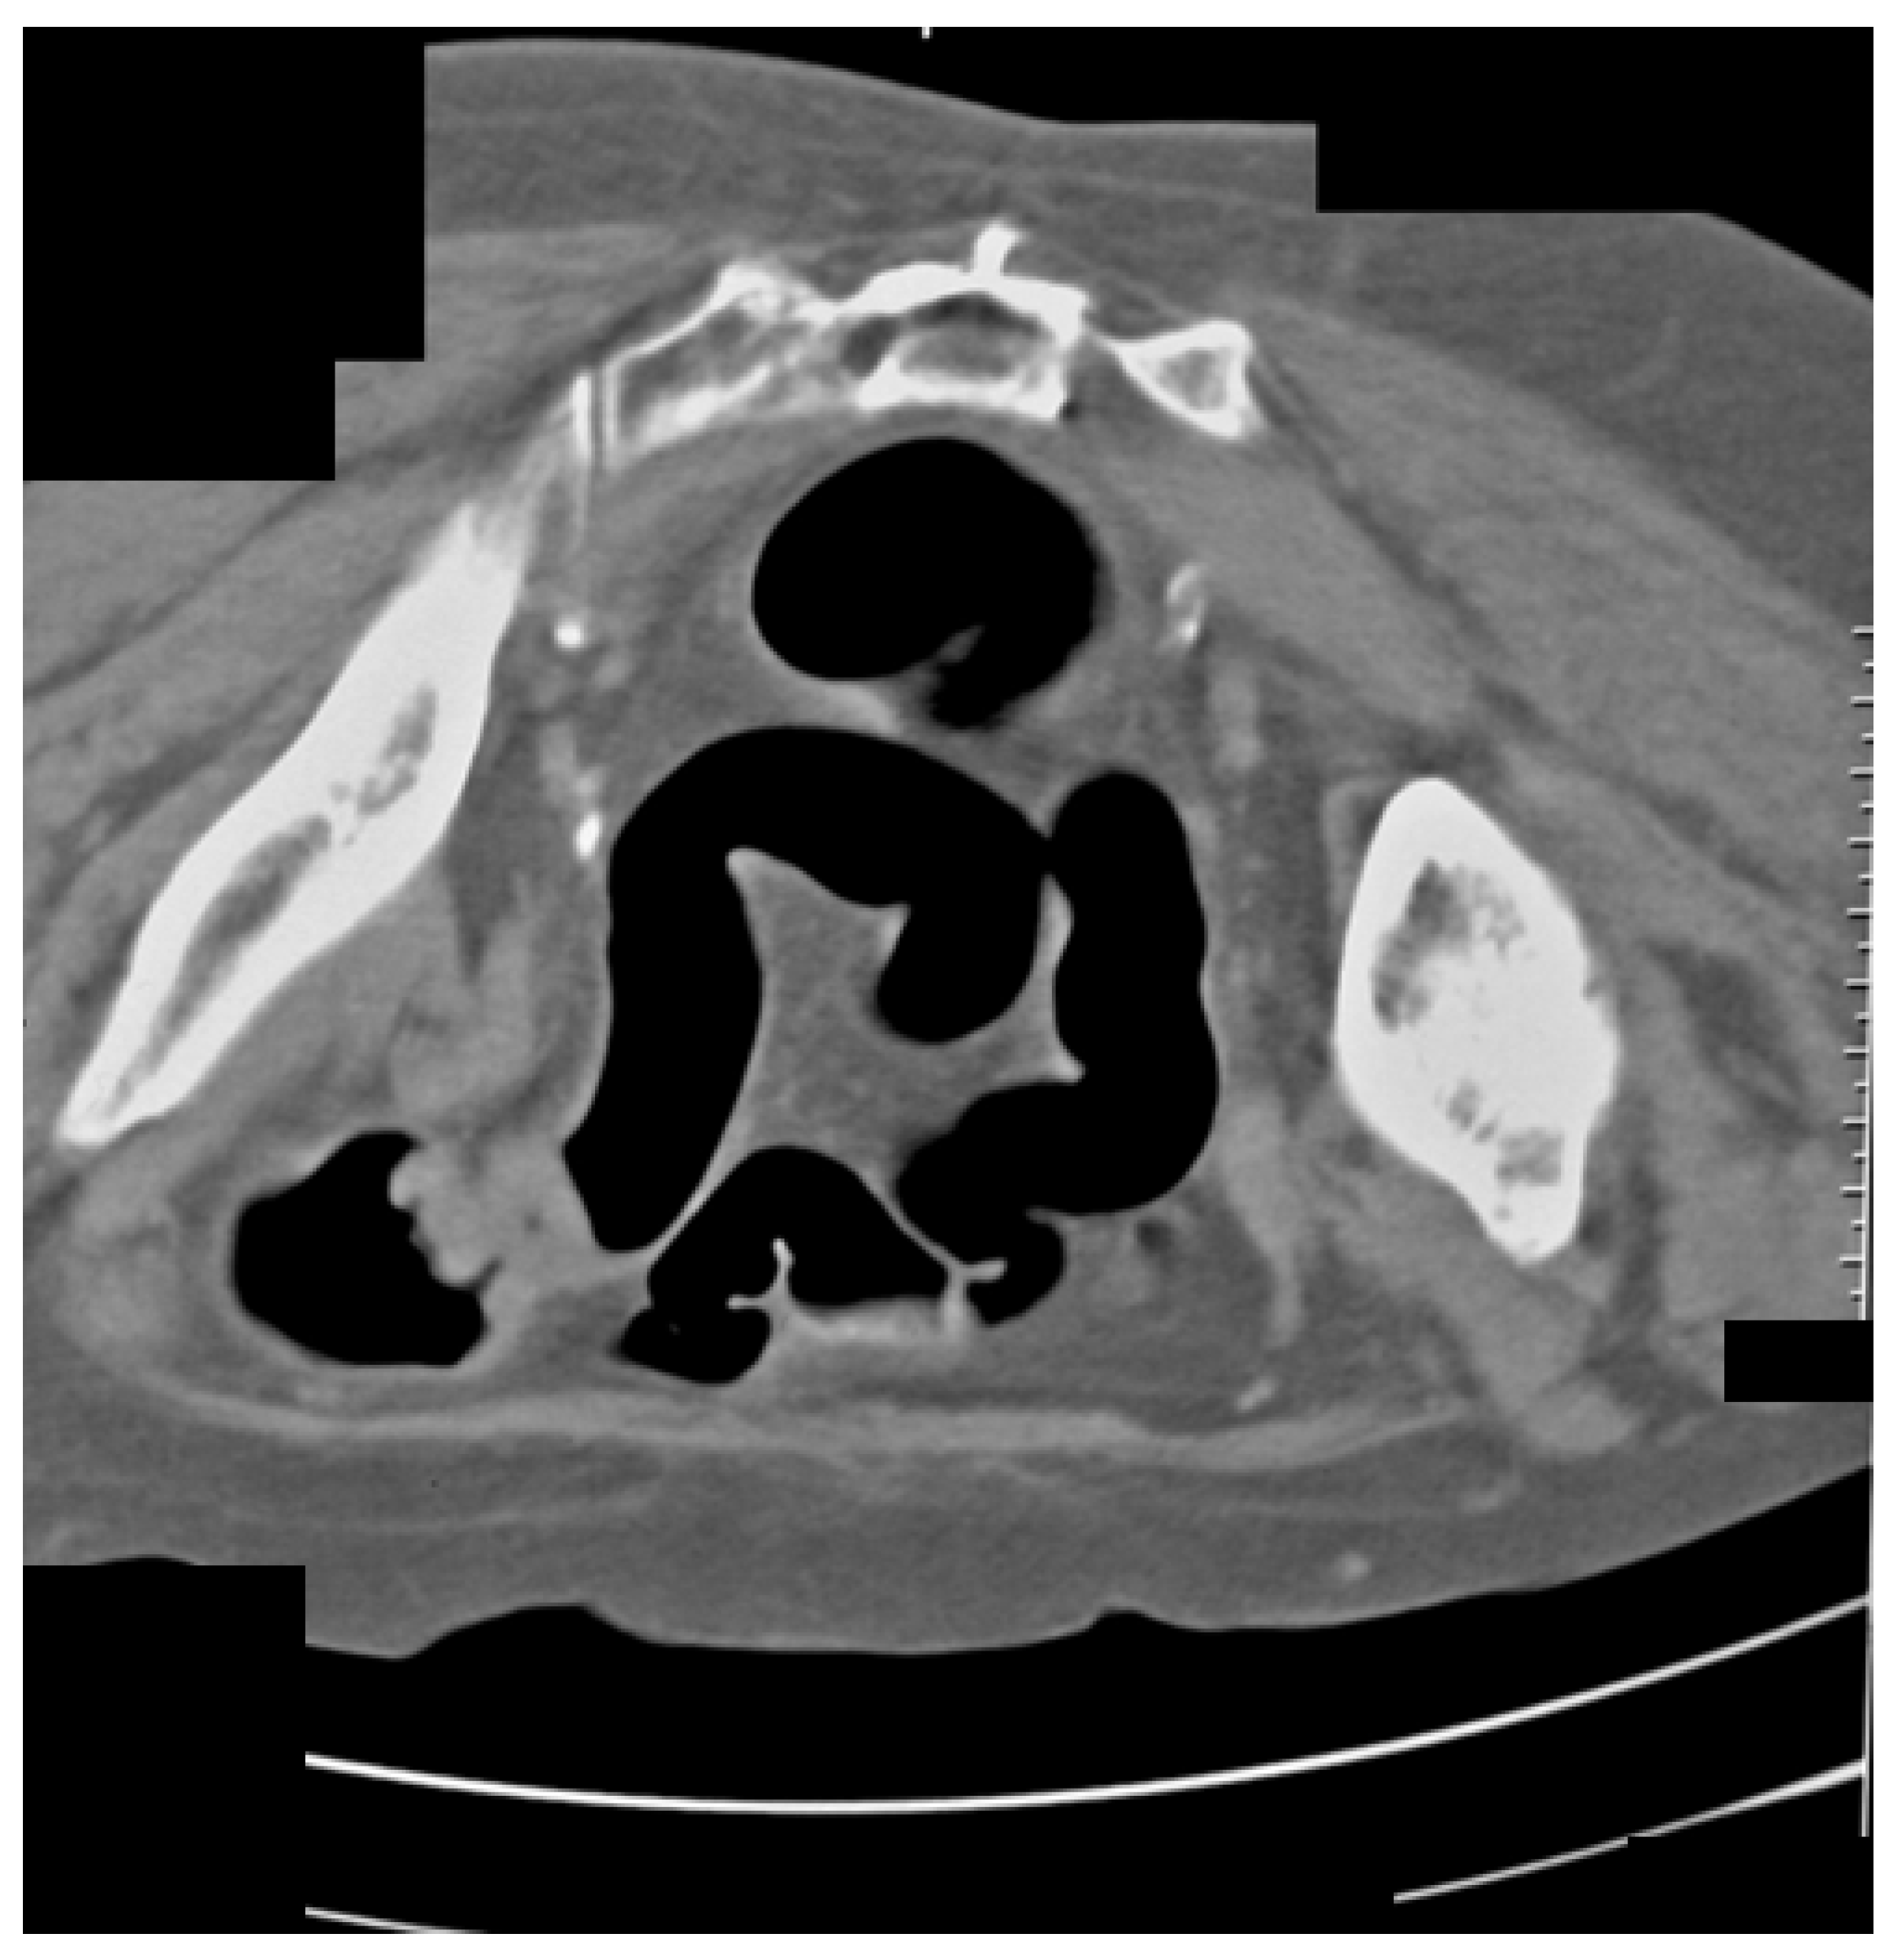

Figure 5 shows a 67-year-old female with flank pain and transitional spasm. The clinical data suggested intestinal tumors. FCS was performed, and there was evidence of extraluminal formation, compressing the colon. Afterward, CT colonography was performed, on which tumor formation arising from the left ovary was observed.

Figure 5.

CT colonography–axial slice in a supine position. Narrowing of the sigmoid colon due to a large ovarian tumor in the left is presented (yellow arrow). FCS did not detect any abnormalities.